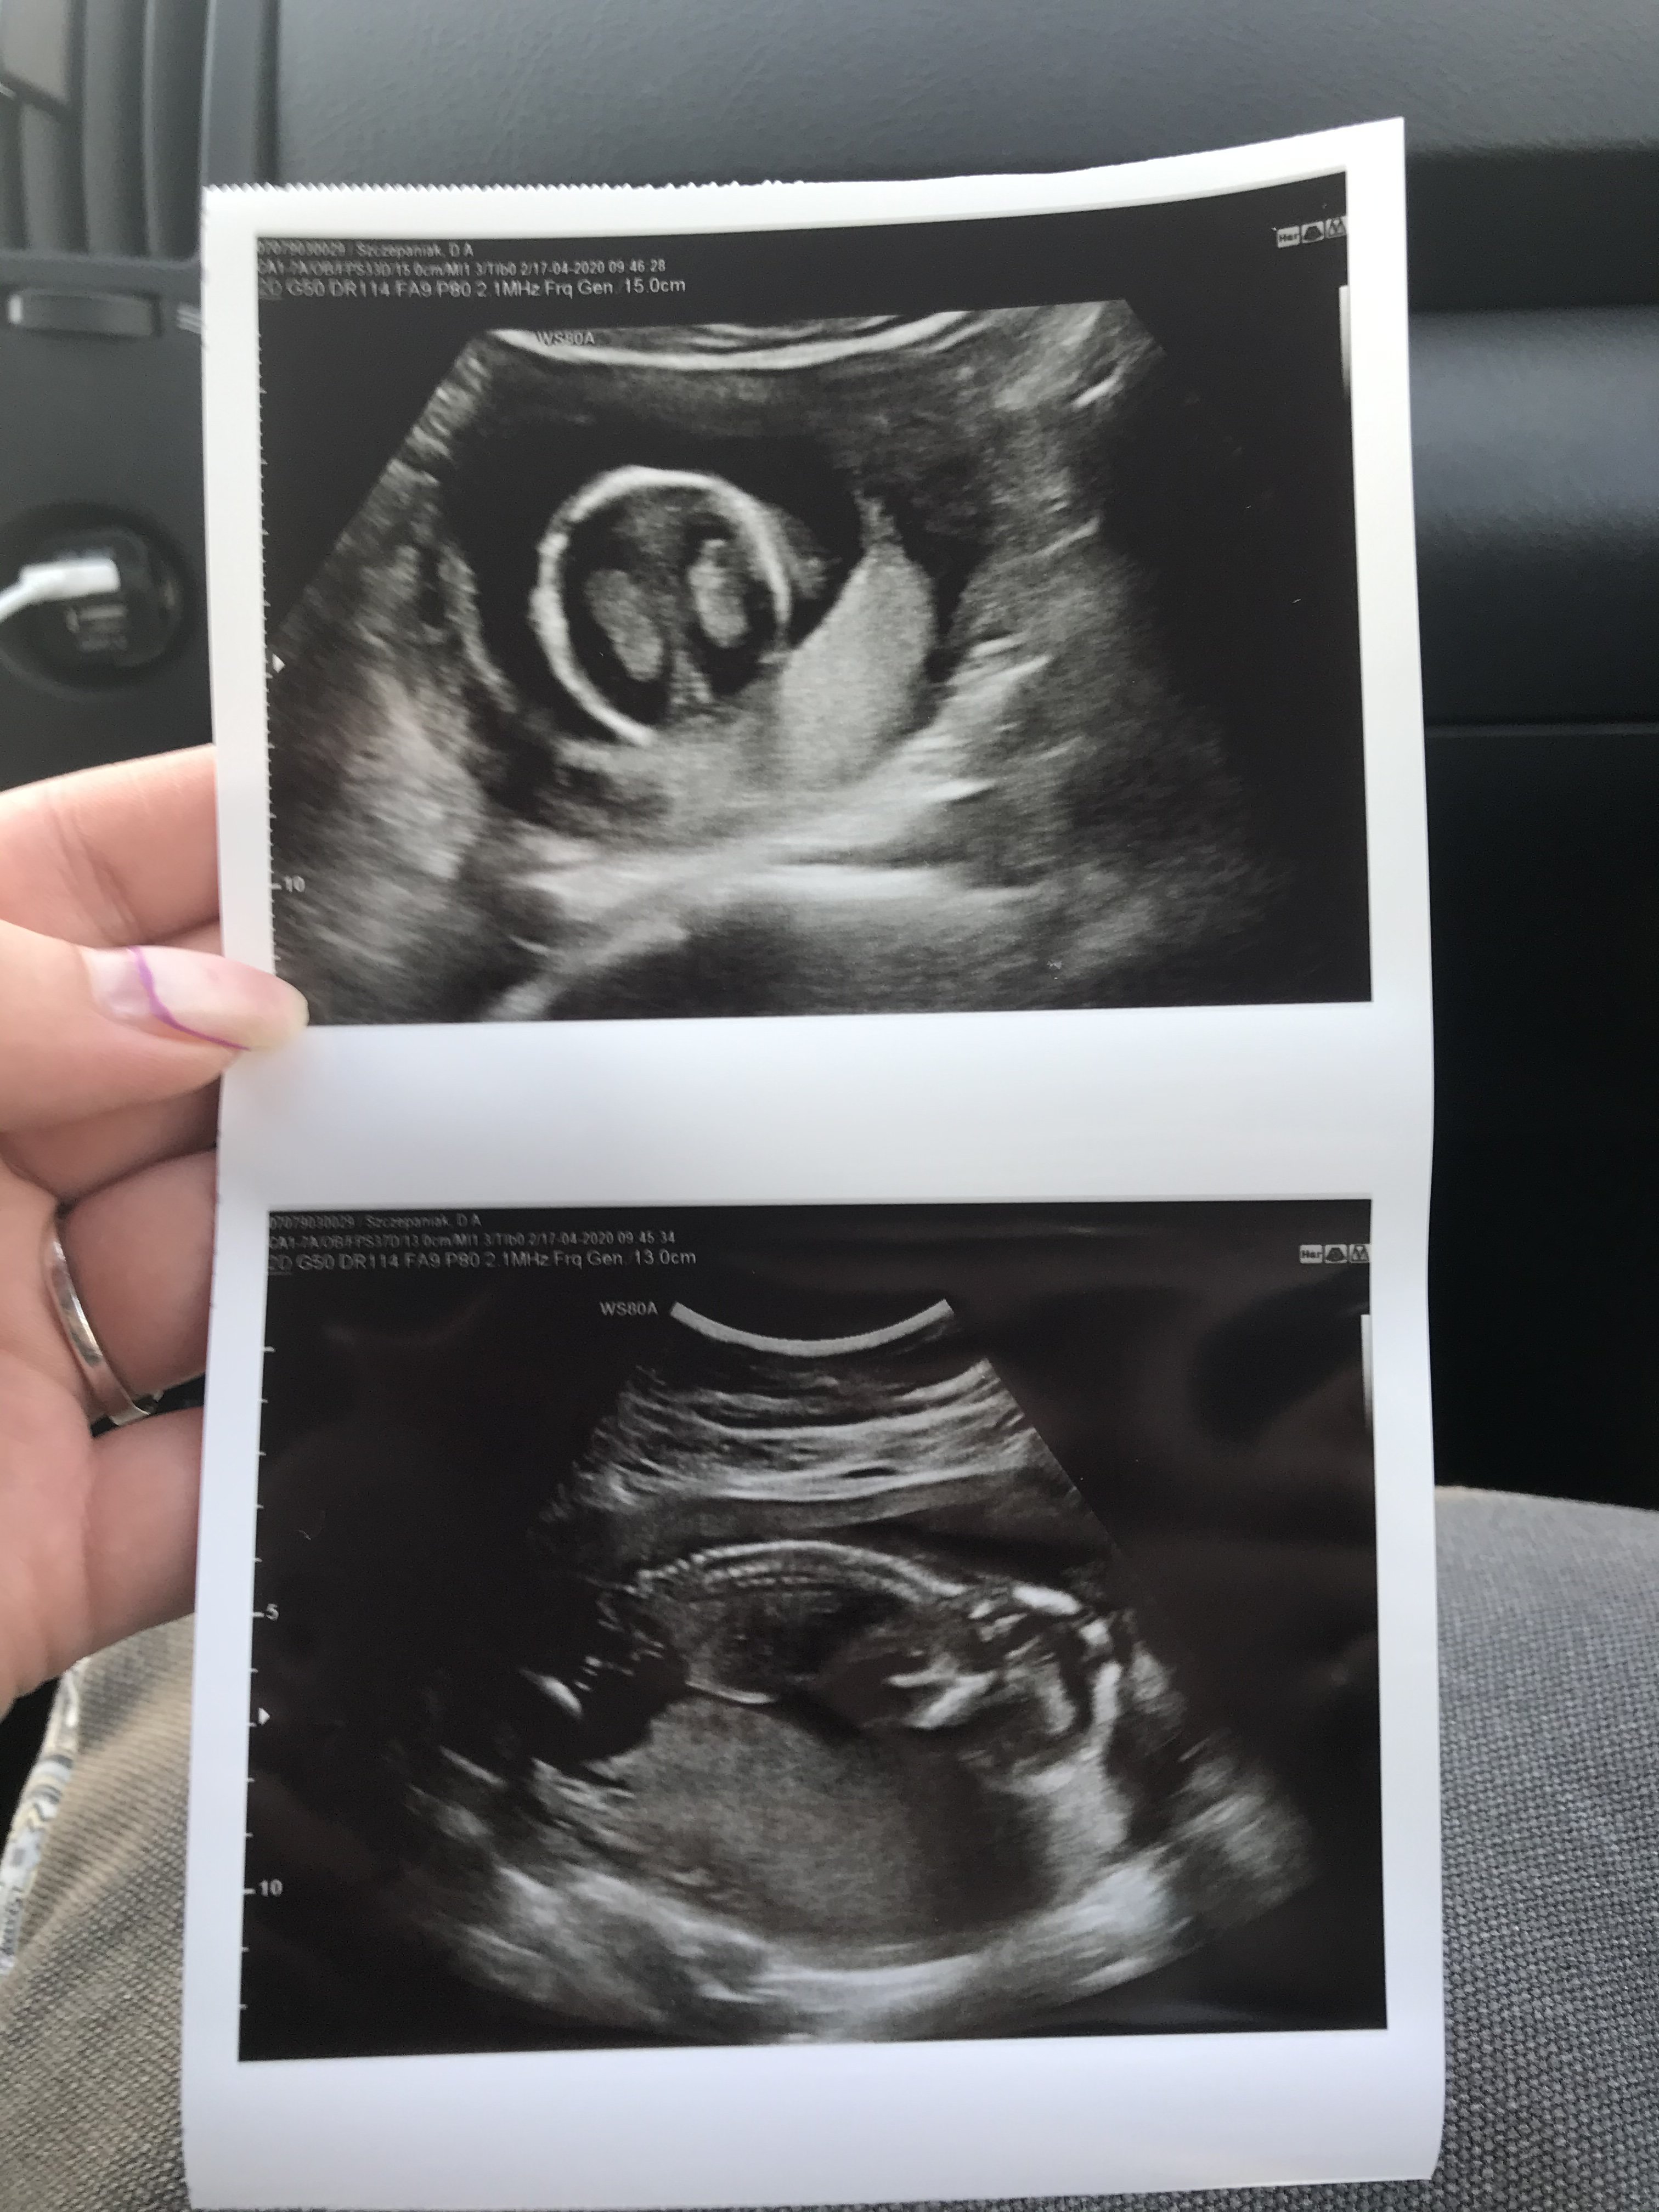

Wróciłam z usg, trwało max 5min....

Mamy 2 półkule mózgu, wątrobę i zalazki płuc, puściła na samym początku bicie serca bo maluch spał grzecznie w dziwnej pozycji - jak matka 😂

Serce bije miarowo i prawidłowo,

mamy 10cm długości

Kolejne usg 18.05 - połówkowe

Zapytałam o płeć to powiedziała ze za wcześnie 🤦🏽‍♀️ Muszę czekac do maja

A to nasz model/ka